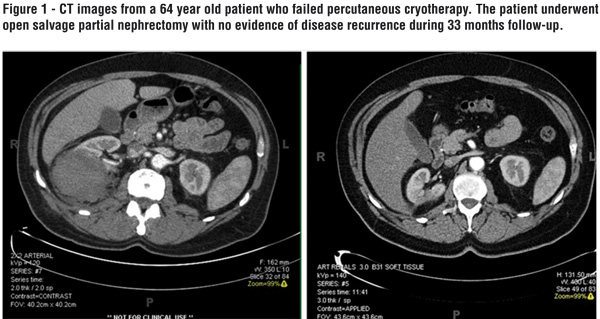

The mean follow-up was 32.9 months (3.5-88 months) and during this period only 1 patient experienced cancer recurrence 6 months following the salvage procedure. The patient underwent a combination of radiation therapy to a lumbar vertebral metastasis and tyrosine receptor kinase therapy. Three of our patients experienced complications including prolonged ileus, cecal volvulus and a urinary fistula. All of the patients were treated conservatively consisting of nasogastric tube decompression, endoscopic decompression and double J stent (Figure-1).